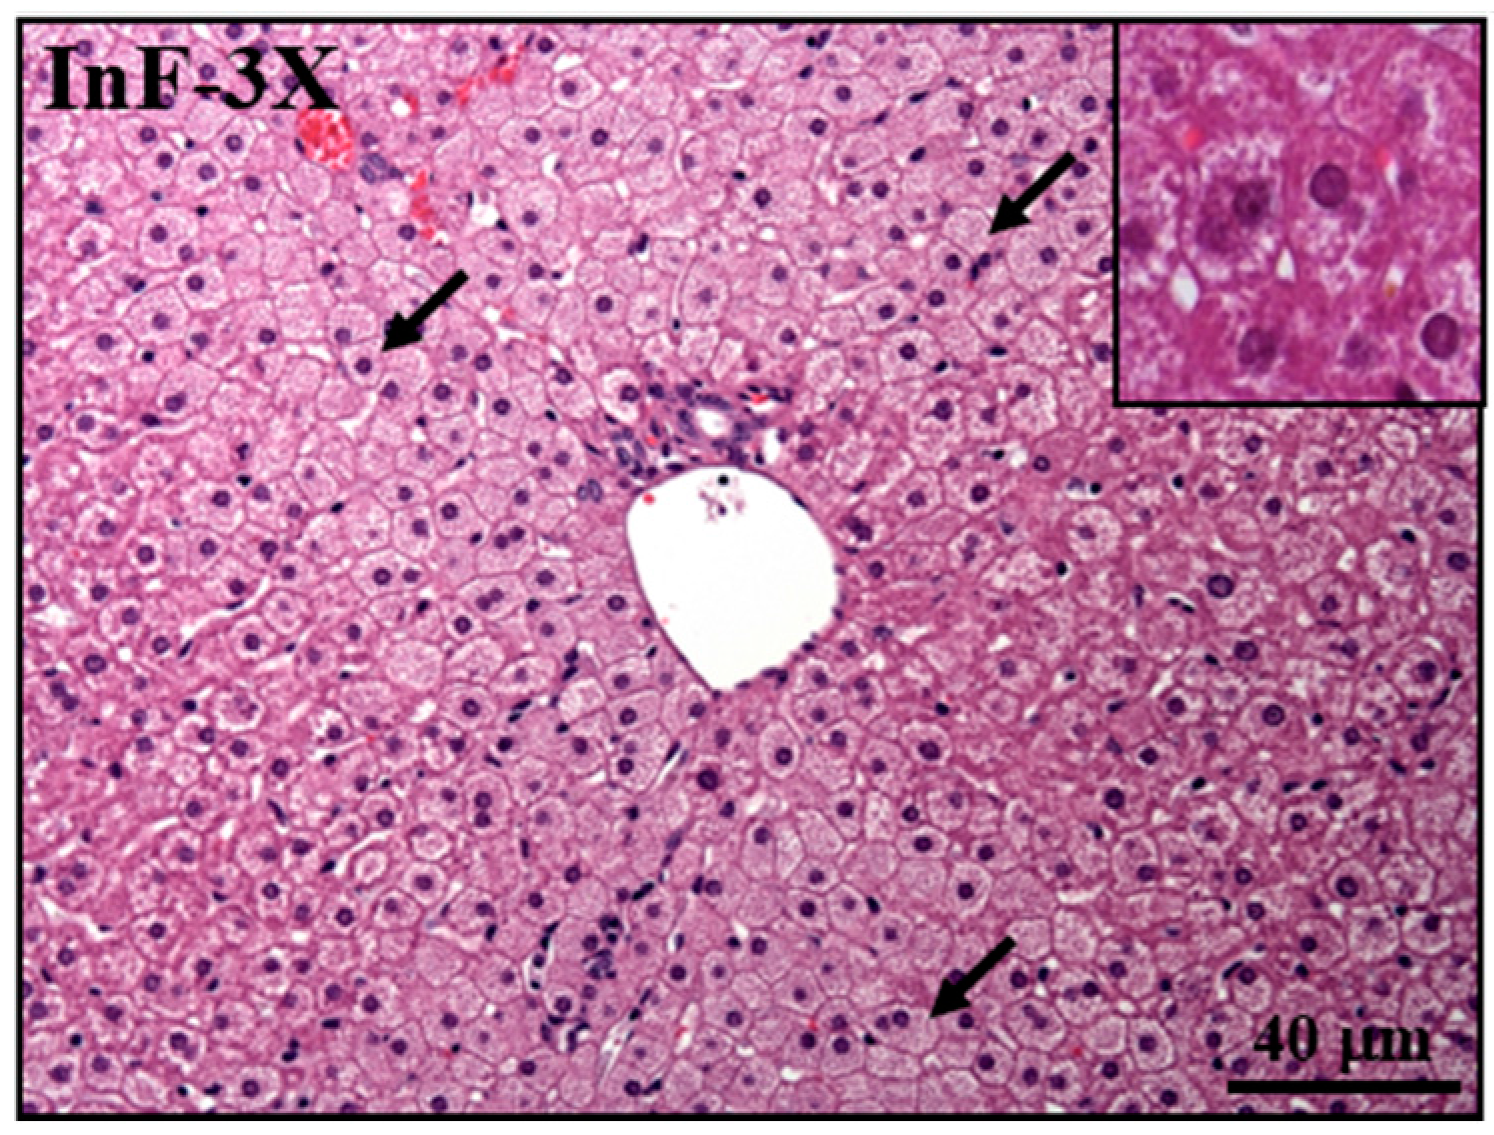

2.8. Effect of InF Supplementation on Tissue Features